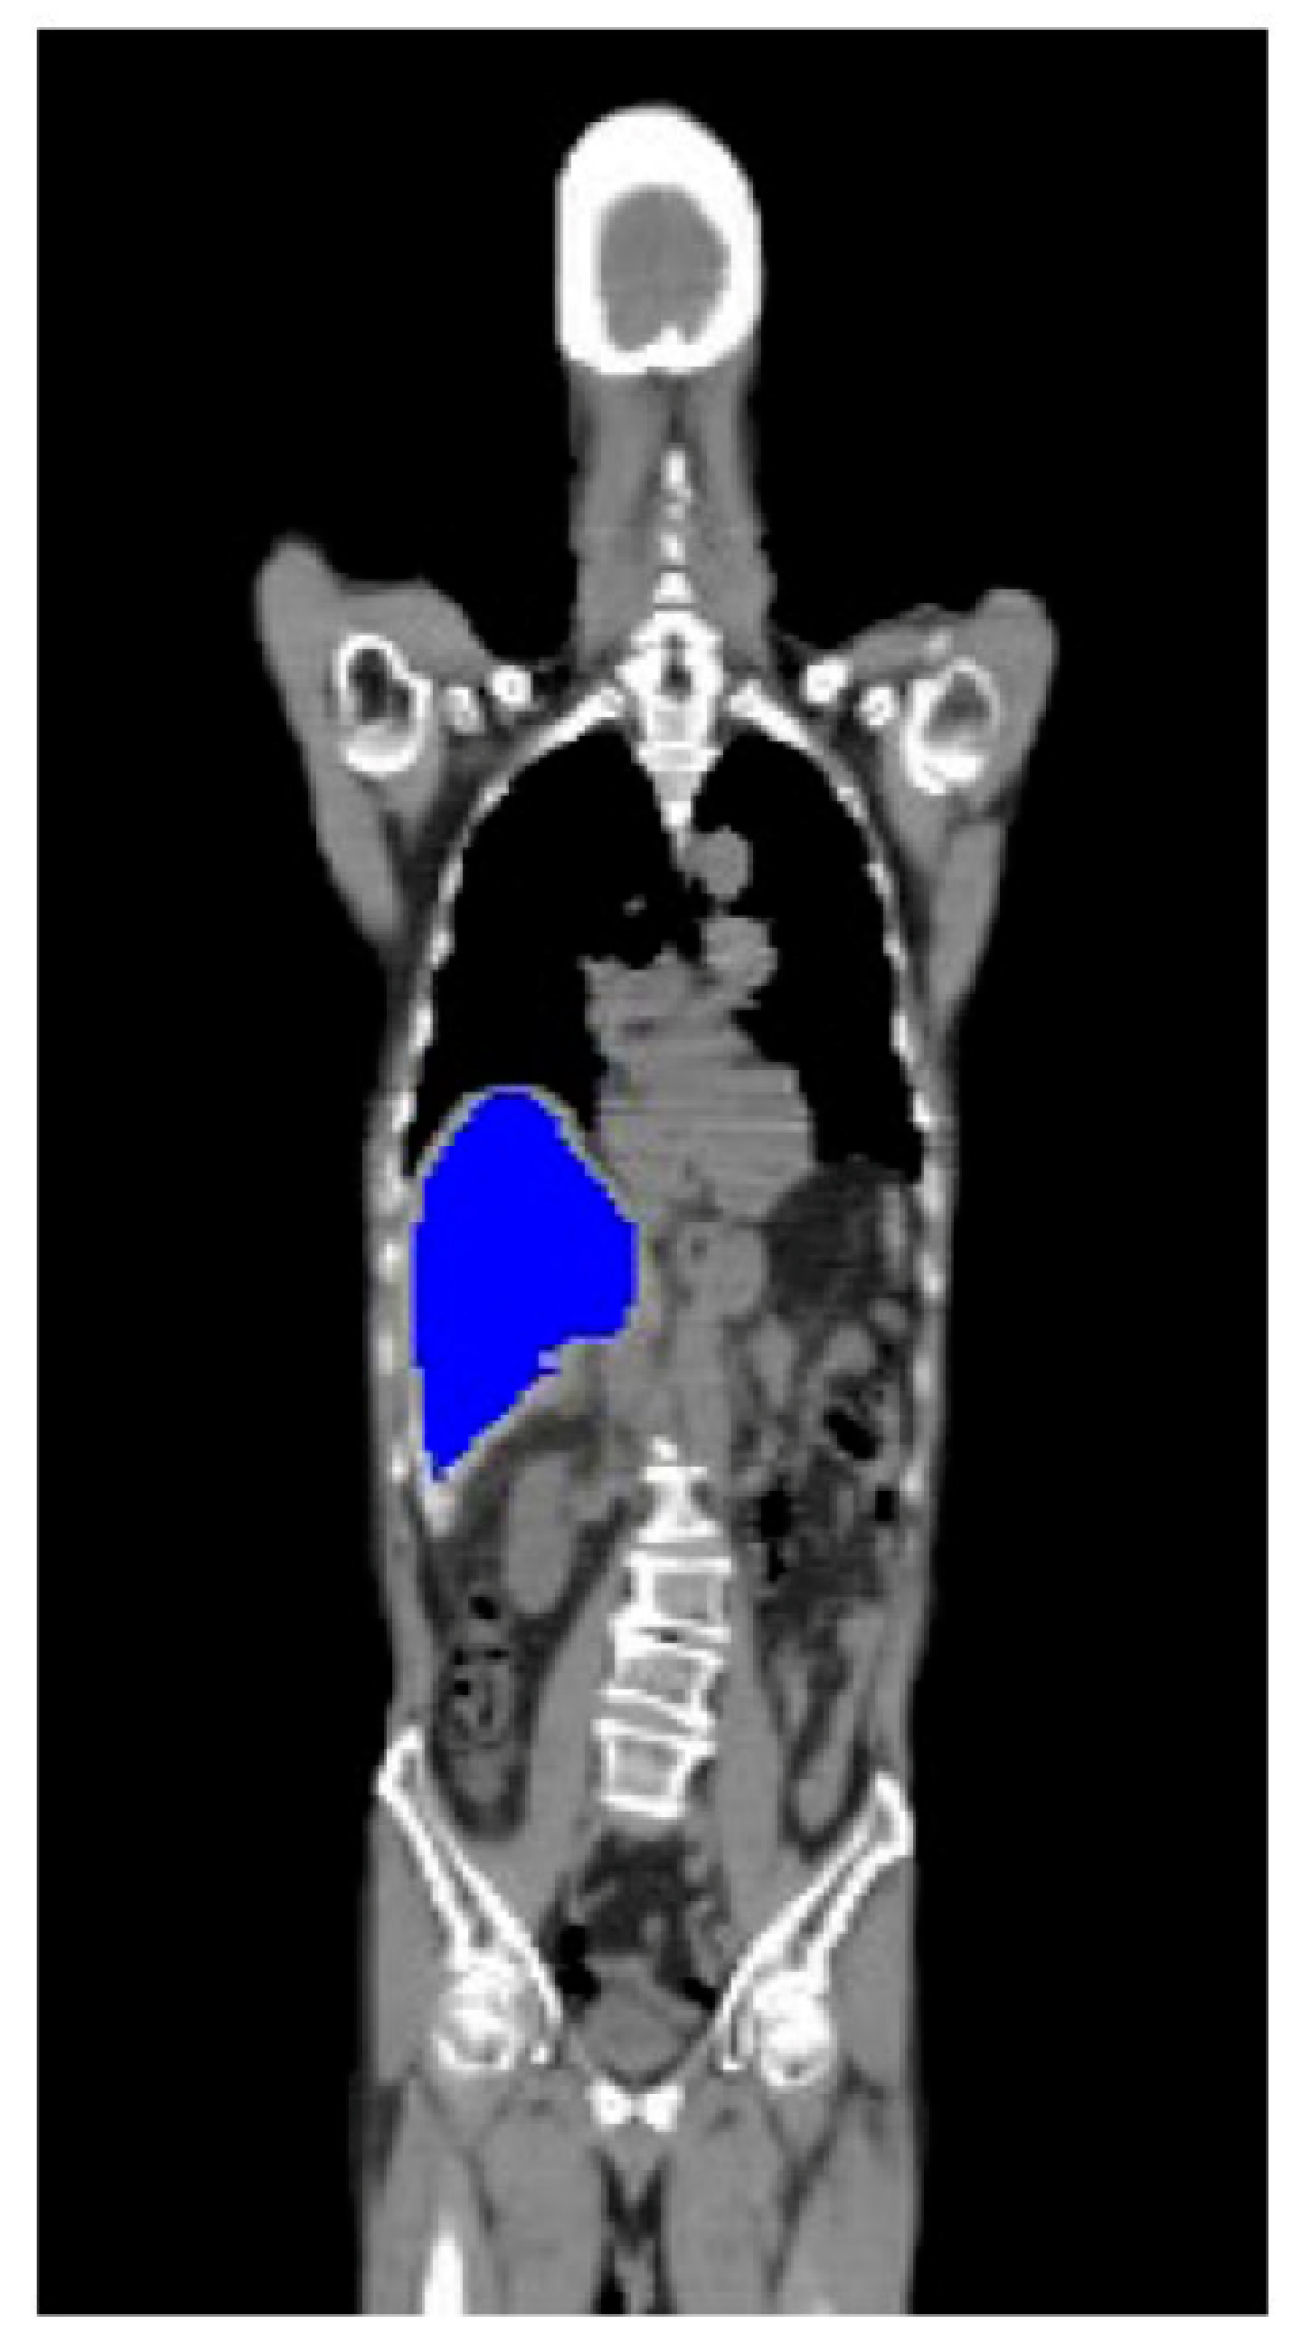

2.3. Image Preprocessing